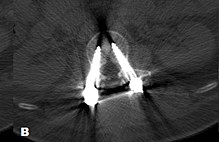

Repetitive stress/trauma results in osteoarthritis that causes inflammation and joint fluid [8]. This chronic degenerative inflammation and stress, combined with cystic deformation of the synovial lining of the joint, leads to the formation of lumbar facet cysts. The cysts originate from the synovium of the facet joint and frequently remain in continuity. Biomechanical studies have shown that as the normal disc segment degenerates, the mechanical load shifts from the anterior column to the posterior column, which includes both facet joints. It has been experimentally demonstrated that disc degeneration creates a five-fold increased load on the facet joints. Over time, this marked increased load leads to a progressive synovial reaction, and inflammatory fluid formation, which is the basis of the pathophysiology leading to the development of facet cysts. Eventually, there is bone proliferation, facet hypertrophy, and segmental degeneration, instability, and stenosis [9]. Additional chronic hypermobility, secondary to increased joint loading and stretching of the facet capsule ligament, can lead to increased fibrocartilage reaction. This lays the groundwork for the formation of these cysts [9-11]. In a study examining 45 cysts resected during surgery, a communication channel between the cyst and the joint was confirmed in the majority of cases [12]. The involved facet joint also showed moderate to severe degeneration. When the cyst and facet joints were studied pathologically, the cyst walls consisted of elastic and collagen fibers undergoing fibrinoid degeneration, but no synovial lining cells were detected [12]. Associated ligamentous hypertrophy and/or degenerative anterolisthesis adds further compression and stress to the facet joint capsule [13]. If a cystic outpouch forms and the cyst enlarges, it can encroach upon the neuroforamen or spinal canal, often leading to nerve root compression [9, 14-15]. In computer studies of the facet joints, clear deformities in the middle of the facet capsular ligament (FCL) were found. Anterior capsular deformations were more noticeable than posterior ones, as the typical facet cyst develops anteriorly [15]. In large clinical and radiographic series of lumbar facet cysts, the L4-5 level was the most affected (82%) and grade I spondylolisthesis was seen in 47% of cases [16-18]. Examples of different facet cysts with axial MRI studies demonstrate the various sizes and typical ventrolateral location of lumbar facet cysts as well as the associated fluid formation within the adjacent facet joint (Figure 4).